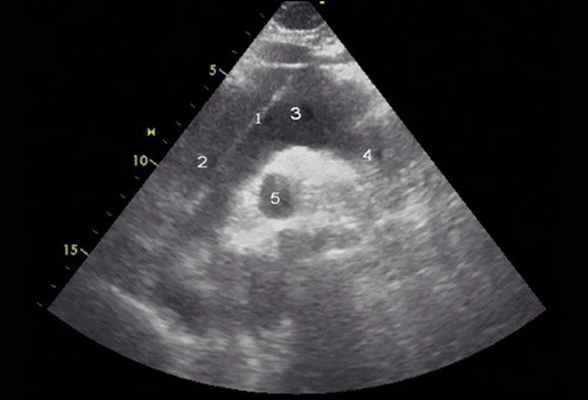

Рис. 4. Эхокардиограмма больного Ж. Супрастернальная позиция.

1 - отслоенная интима аорты, 2 - восходящий отдел аорты, 3 - дуга аорты, 4 - нисходящий отдел аорты, 5 - правая ветвь легочной артерии.

Помимо гипертрофии миокарда левого желудочка, склеротически измененных створок аортального клапана и наличия его недостаточности I степени, обращало на себя внимание расширение восходящего отдела аорты до 4,5-5,1 см (на различных уровнях) (рис. 1). Исследование средних отделов восходящей аорты (рис. 2) позволяло выявить нитевидную, невыраженно флотирующую структуру, расположенную по передней стенке аорты, формирующую истинный и ложный каналы аорты, которые более детально верифицировались в режиме ЦДК (рис. 3). В слепом участке ложного канала определялись тромботические массы. При исследовании из супрастернального доступа в области дистального отдела восходящей аорты и ее дуги лоцировался участок отслоения интимы (рис. 4). В остальных отделах аорты, доступных для визуализации, патологии выявлено не было. Таким образом, ультразвуковое исследование сердца позволило диагностировать расслаивающую аневризму восходящего отдела и дуги аорты (тип II по De Bakey). Проведенная МСКТ подтвердила данный диагноз (рис. 5).